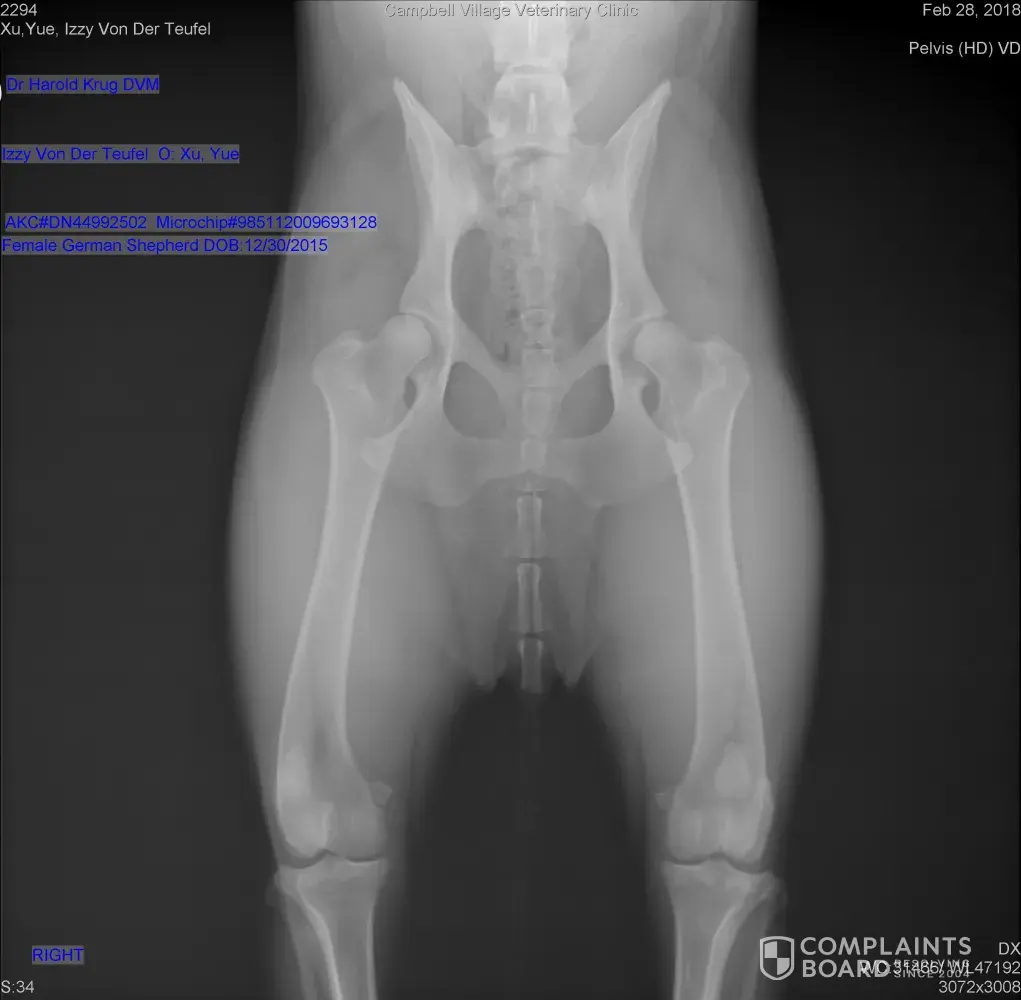

In Fed 2018, I paid almost $600 to get my dog OFA X-ray exam after she reaches 24 months old. She was diagnosed with mild hip dysplasia. I contacted with the breeder and sent him all X-ray films and document. He told me the dog will have a normal life, and offered me a replacement. But, the dog will not have a normal life with hip dysplasia, and I will potentially pay big money for her hip dysplasia in her later life. Also, I will not trade her to another pup, she's one of the family already. Obviously, the breeder knew this when he gave the health guarantee. No one will trade their own dog for a NEW pup. This breeder treats dog as merchandise which I can't do it. With this health guarantee, I got no compensation but a hip dysplasia dog. He said he offered what he offered me when I picking up the pup. I didn't realize when he said "replace" literally means to return my dog and get a new pup. I requested a refund, but he refused and didn't reply my message. I messaged him the vet said the dog's siblings may have same problem. of course, he didn't reply at all.

The first dog in question had good hips. X-rays could be done again when the dog is within heats. and she would pass. I offered the buyer a replacement if she returned her and she refused and wanted money back and then started insulting me so I stopped responding to her. I have this dogs full sister and she has OFA good hips and normal elbows.

Text messages from mx100. Offered her replacement and she refused. She wanted money back and to keep the dog. There’s nothing wrong with her dogs hips. If her vet thought they were bad then he wouldn’t have sent them to OFA for evaluation. As to AJ I can go on for days about him and how his dog jumped off a parking garage destroying his elbow. He’s also a felon. All our puppies receive the required vaccines, wormings, vet visit for health check, and come with shot records. There is nothing shady about us. We have been doing this since 2008 and these are our only two complaints. Read the complaints and you’ll see both admit to being offered the warranty but they refused. AJ Millers from MillerhausK9 cane back after his warranty was expired knowing his dog jumped off a parking garage and was hoping to get something for free to make up his mistake. Xu Yue could have retaken xrays and passed or just exchanged the dog. We would have evaluated the dog for the right home and probably charged a very reasonable fee for her. Having her full sister she probably would do well in a home with small children needing a protection dog